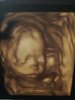

Połówkowe - wyniki

OM 21+4 tc

USG 21+1 tc

Wszystkie narządy prawidłowe

Waga: 420 g

Tętno 148

Szyjka 4,6

Płeć : dziewczynka